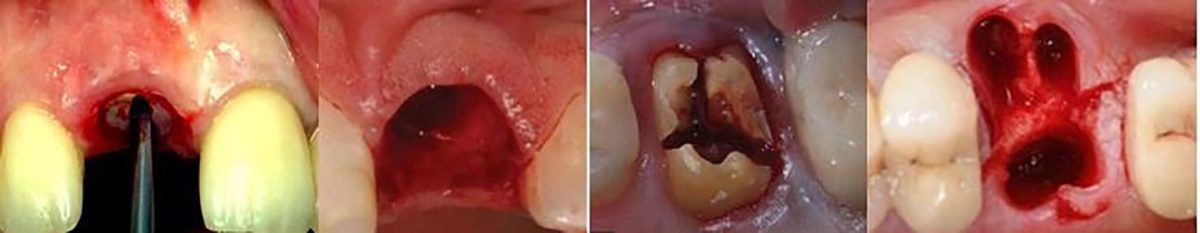

MQI Atraumatic Extraction Tools: It is imperative today that the clinician understands the consequences of tooth extraction relating to the hard and soft tissues. It has become the standard of care to preserve these tissues whenever possible for long-term oral health, function and esthetics.

Atraumatic Extraction & Socket Development: Atraumatic extraction & socket management leads to a predictable foundation for the implant treatment, preserves the quantity and quality of bone along with the gingival architecture. This will ultimately lead to more predictable implant positioning and placement. Removing the tooth with no/minimal hard or soft-tissue damage is ideal for healing, regeneration and maintenance of existing bone. [7]

The Periotome Extraction Technique:

The periotome, is the most commonly used tooth extraction instrument [8] with a very thin tip -a tapering blade- can be inserted in the space between the tooth and the surrounding bone compresses the bone structure slightly allowing better access to the periodontal ligament which can then be cut with ease. The instrument is then pushed deeper into the periodontal ligament space/tapped with a mallet into the space along the mesial and distal root, severing the periodontal ligament immediately below the alveolar crest and wedging the tooth against the opposing cribriform plate.

Insert more apically, and do a persistent vertical motion – until the tooth becomes lose and then avulse it out steadily. Conventional extraction techniques often result in fracture of the buccal or lingual alveolar plates which leads to compromised healing. The periotome should never be used on the facial plate.